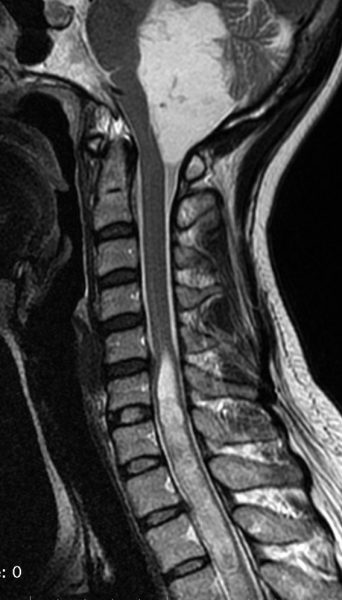

脊髄空洞症 syringomyeliaの合併

上と同じ患者さんです。大後頭孔での髄液流が悪くなるため,また腫瘍が何年もかかってゆっくり大きくなるので,脊髄に空洞ができました(脊髄空洞症)。脊髄の内部が裂けてしまうので,強い胸部の疼痛がでて発症しました。

第4脳室腫瘍を摘出するとこの空洞症は自然に治るので,何もしません。また症状も良くなることが多いです。

幼児の延髄に発生して第4脳室に伸展した毛様細胞性星細胞腫に合併した脊髄空洞症です。

ちなみにこれは毛様細胞性星細胞腫に合併する脊髄内のう胞ではありません。

この例の場合は,原因となった延髄腫瘍が摘出できないので,難治性の脊髄空洞症になります。